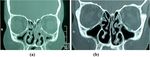

Fig. 1 CT of group A. a Pre-operative CT showing maxillary and ethmoid sinusitis. b Post-operative CT showing aireated maxillary sinus with very

mild ethmoid sinusitis

(Figs. 1 and 2 and Supplementary Figure 1) according to

Post-operative CT finding according to the Lund and                      preted considering history, examination, and response to

Mackey score in group A decreased significantly from                        medical treatment [2].